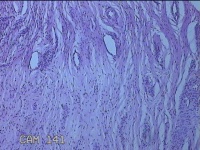

宫颈6点、12点组织

性别

女

年龄

33岁

临床诊断

人乳头瘤病毒感染

一般病史

发现HPV18,其他12种阳性近一月。

标本名称

大体所见

1.“宫颈6点组织”:灰白粉红色组织0.5x0.3x0.2cm一块。 2.“宫颈7点组织”:灰白暗红色组织0.8x0.3x0.2cm两块。

图3